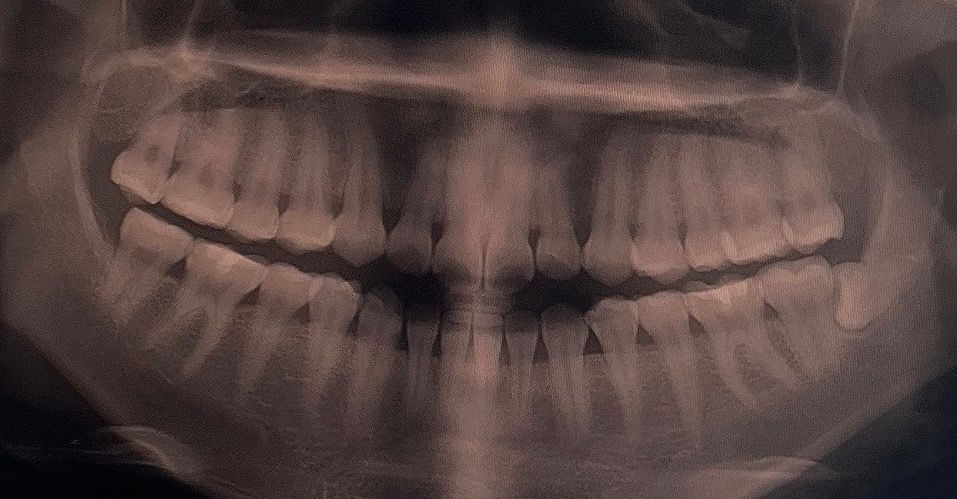

혹시몰라 사랑니 발치 전 파노라마 사진 올립니다..

(오른쪽 위 어금니, 왼쪽 아래•윗 어금니 충치치료 완료했습니다)

선생님들이 보시기에도 파노라마로 보는 구강상태가 좋지않은지도 말씀부탁드립니다ㅠㅠ

엑스레이상으론 뾰루지 농양의 기원이 치아 때문은 아닌 것 같고 잇몸 원인의 치주 농양같습니다. 신경치료 보다는 잇몸치료 해보고 증상 지켜보면 좋을 것 같습니다.